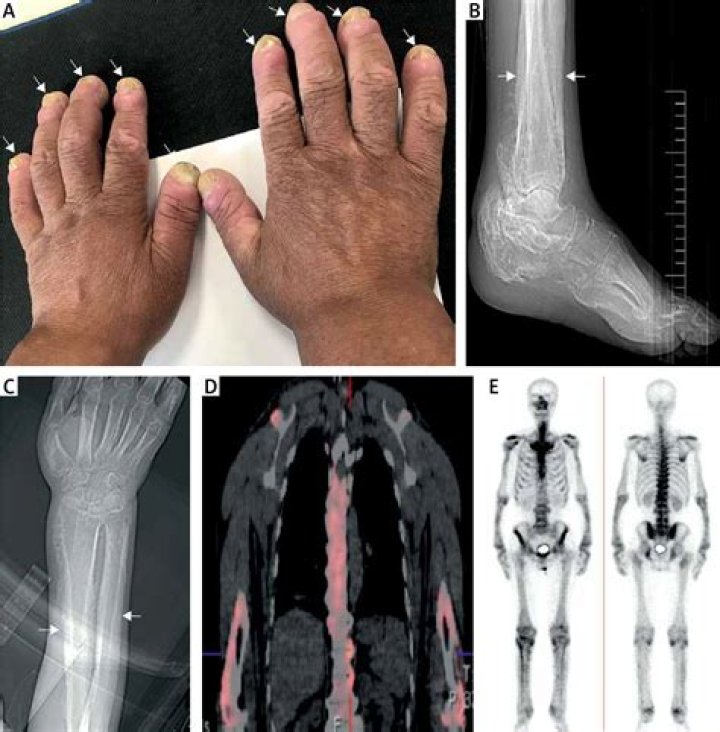

Hypertrophic pachymeningitis is a rare form of diffuse inflammatory disease that causes thickening of the dura mater. It can involve the cranial or the spinal dura or both.